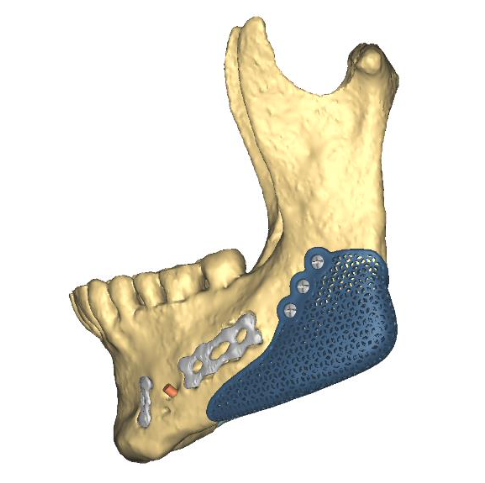

The filler is aimed at making my gonial angle better and my jaw width better.